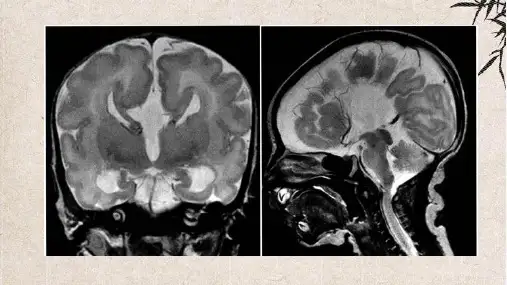

2、CT表现两侧侧脑室显著分离,枕角相对不对称扩大;胼胝体发育不全时,可见侧脑室前角狭窄、向外侧分离,呈倒八字形,侧脑室体部与前角顶端呈锐角向侧方突起;由于脑组织异位,侧脑室边缘不规则。

由于胼胝体缺如,纵裂池接近第三脑室,有时可见纵裂的蛛网膜囊肿;第四脑室抬高扩大,上移至两侧侧脑室前角之间,前角狭小呈八字形分离。

4、MRI显示本畸形更清楚,正常人胼胝体与脑组织前后径之比≥0.45,胼胝体发育不全者<0.3。

胼胝体发育不良的诊断首先依靠影像学检查,如MRI(磁共振成像)。

通过MRI可以清晰地观察到大脑结构,包括胼胝体。

在正常情况下,胼胝体应该清晰可见,但在发育不良的情况下,可能完全缺失或部分缺失。

因此,MRI成像是诊断胼胝体发育不良的重要手段之一。

完全性胼胝体缺失时,无胼胝体和透明隔腔形成的复合体,则两侧大脑半球在大脑中部相距较远,双侧侧脑室向左右分开,侧脑室后角扩张,第三脑室扩张并向上移位。